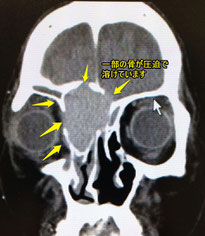

この患者さんも目の内側の重い感じ、痛みにて受診された方です。

篩骨洞という目の内側の副鼻腔に嚢腫という袋ができています。

蓄膿症(副鼻腔炎)の手術を以前に受けた方にまれに見られますが、全く手術を受けたことがない方の例もあります。場合によっては眼を圧迫し、ものが二重に見えたりすることもあります。

こういう嚢腫は、手術で鼻腔側から交通をつけます。